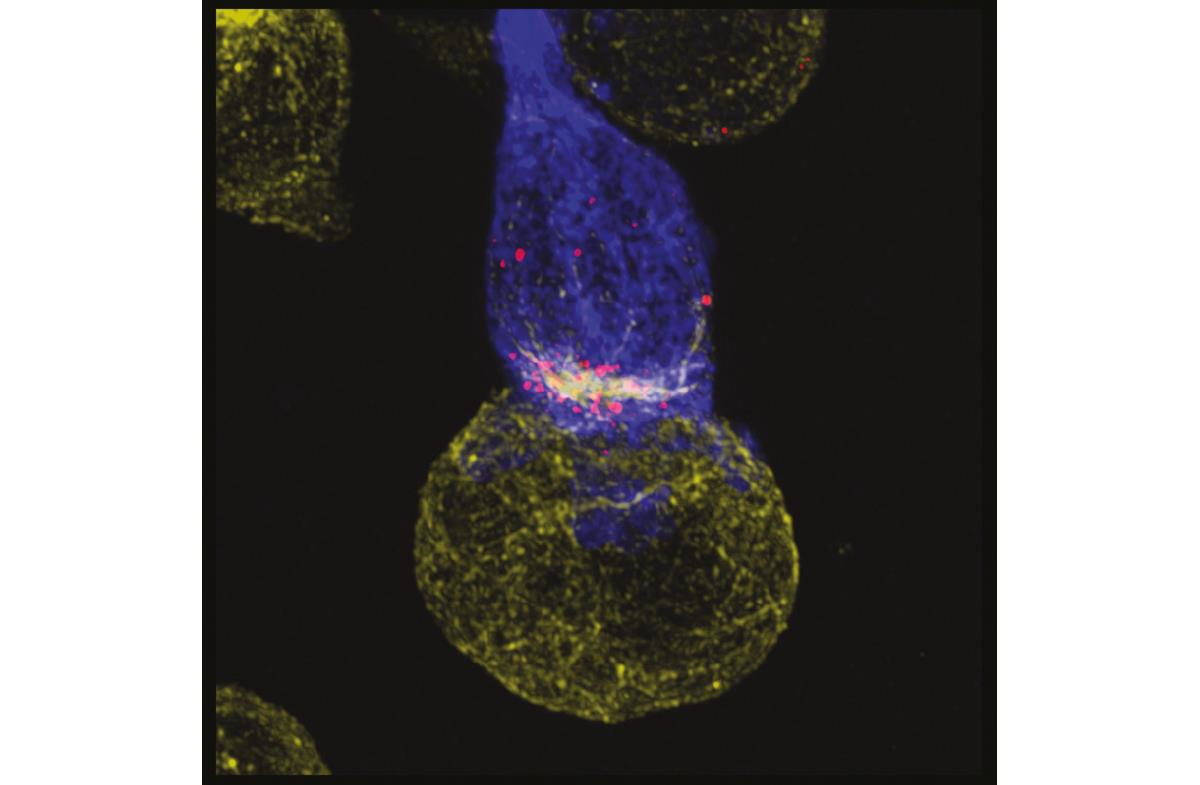

Enkelte gen- og celleterapier faller inn under persontilpasset behandling og er ventet å øke i omfang. Metodene er fortsatt umodne for innføring som etablert behandlingstilbud, og det er kun et lite antall behandlinger på markedet. Norge har imidlertid gode fagmiljøer på dette området, blant annet er det gjennom Forskningsrådet tildelt 155 mill. kroner til et nytt Senter for fremragende forskning for persontilpasset immunterapi ved Oslo universitetssykehus HF. Det nye senteret skal utvikle celleterapi med mål om å kurere flere former for kreft, og dermed behandle flere pasienter.

Foto: Oslo universitetssykehus HF